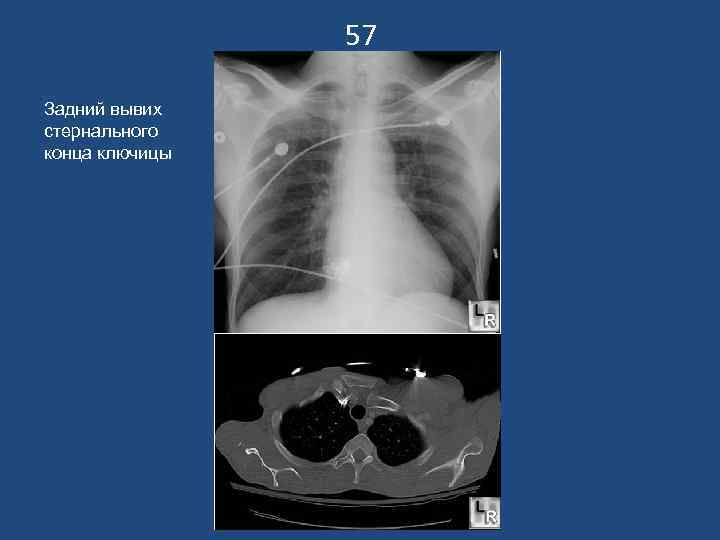

57 Задний вывих стернального конца ключицы